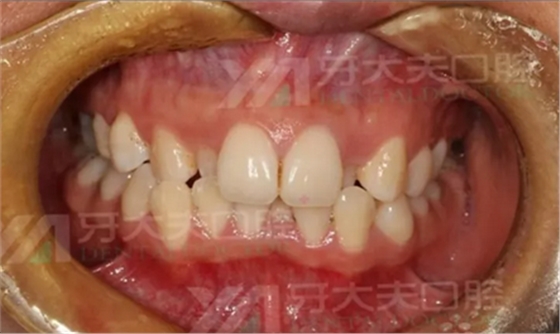

先放一张矫正前的牙齿照片辣一下你们的眼睛。

2016.8.25矫正前